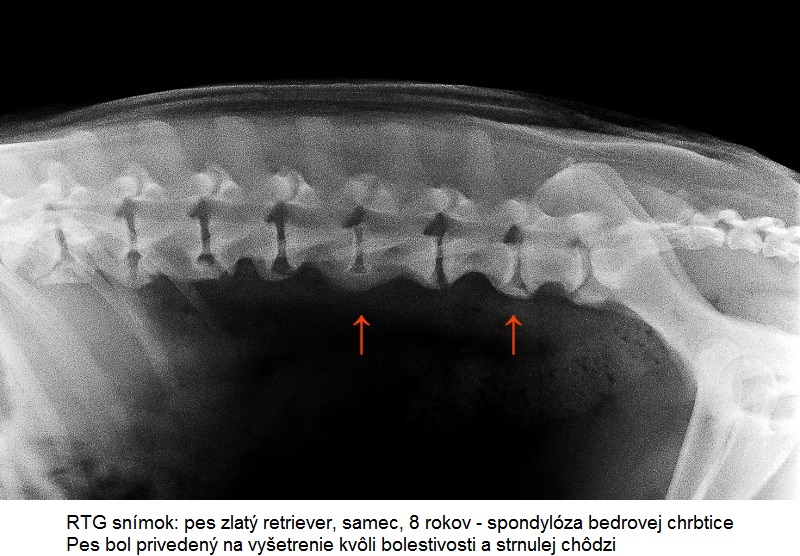

Spondylóza sa diagnostikuje z laterolaterálnej (pes leží na boku), prípadne ventrodorzálnej (pes leží na chrbáte) RTG projekcie. Myelografické vyšetrenie, CT alebo magnetická rezonancia pomôže odhaliť prípadnú kompresiu miechy. Spondylóza môže byť lokalizovaná v priebehu celej hrudnej (Th) a bedrovej chrbtice (L), až po oblasť posledného bedrového a prvého krížového stavca (S). Pričom často sa vyskytuje práve v oblasti prechodu jedného úseku chrbtice v nasledujúci (TH-L, L-S).

Jedná sa o progresívne ochorenie. Veľmi často je diagnostikovaná ako vedľajší nález pri RTG snímkoch zhotovených z iných dôvodov, keďže mnoho postihnutých jedincov ostáva asymptomatických po dlhšiu dobu. Klinicky sa spravidla prejaví až pri strednom a vyššom stupni ochorenia. Nástup klinických príznakov ovplyvňuje viacero faktorov ako plemenná príslušnosť, vek, hmotnosť a záťaž psa. Najčastejšie sa spondylóza prejaví u psov v strednom a vyššom veku, kedy už ani majiteľ neočakáva také fyzické výkony ako u mladšieho psa. Preto môže byť nástup klinických príznakov spočiatku prehliadaný a pripisovaný pribúdajúcemu veku.

Ku klinickým príznakom ochorenia patria: občasné krívanie, zmena kroku (napr. vysoká akcia hrudných končatín), neochota skákať (napr. do kufra auta), chodiť po schodoch, stuhnutosť a bolestivosť chrbtice.